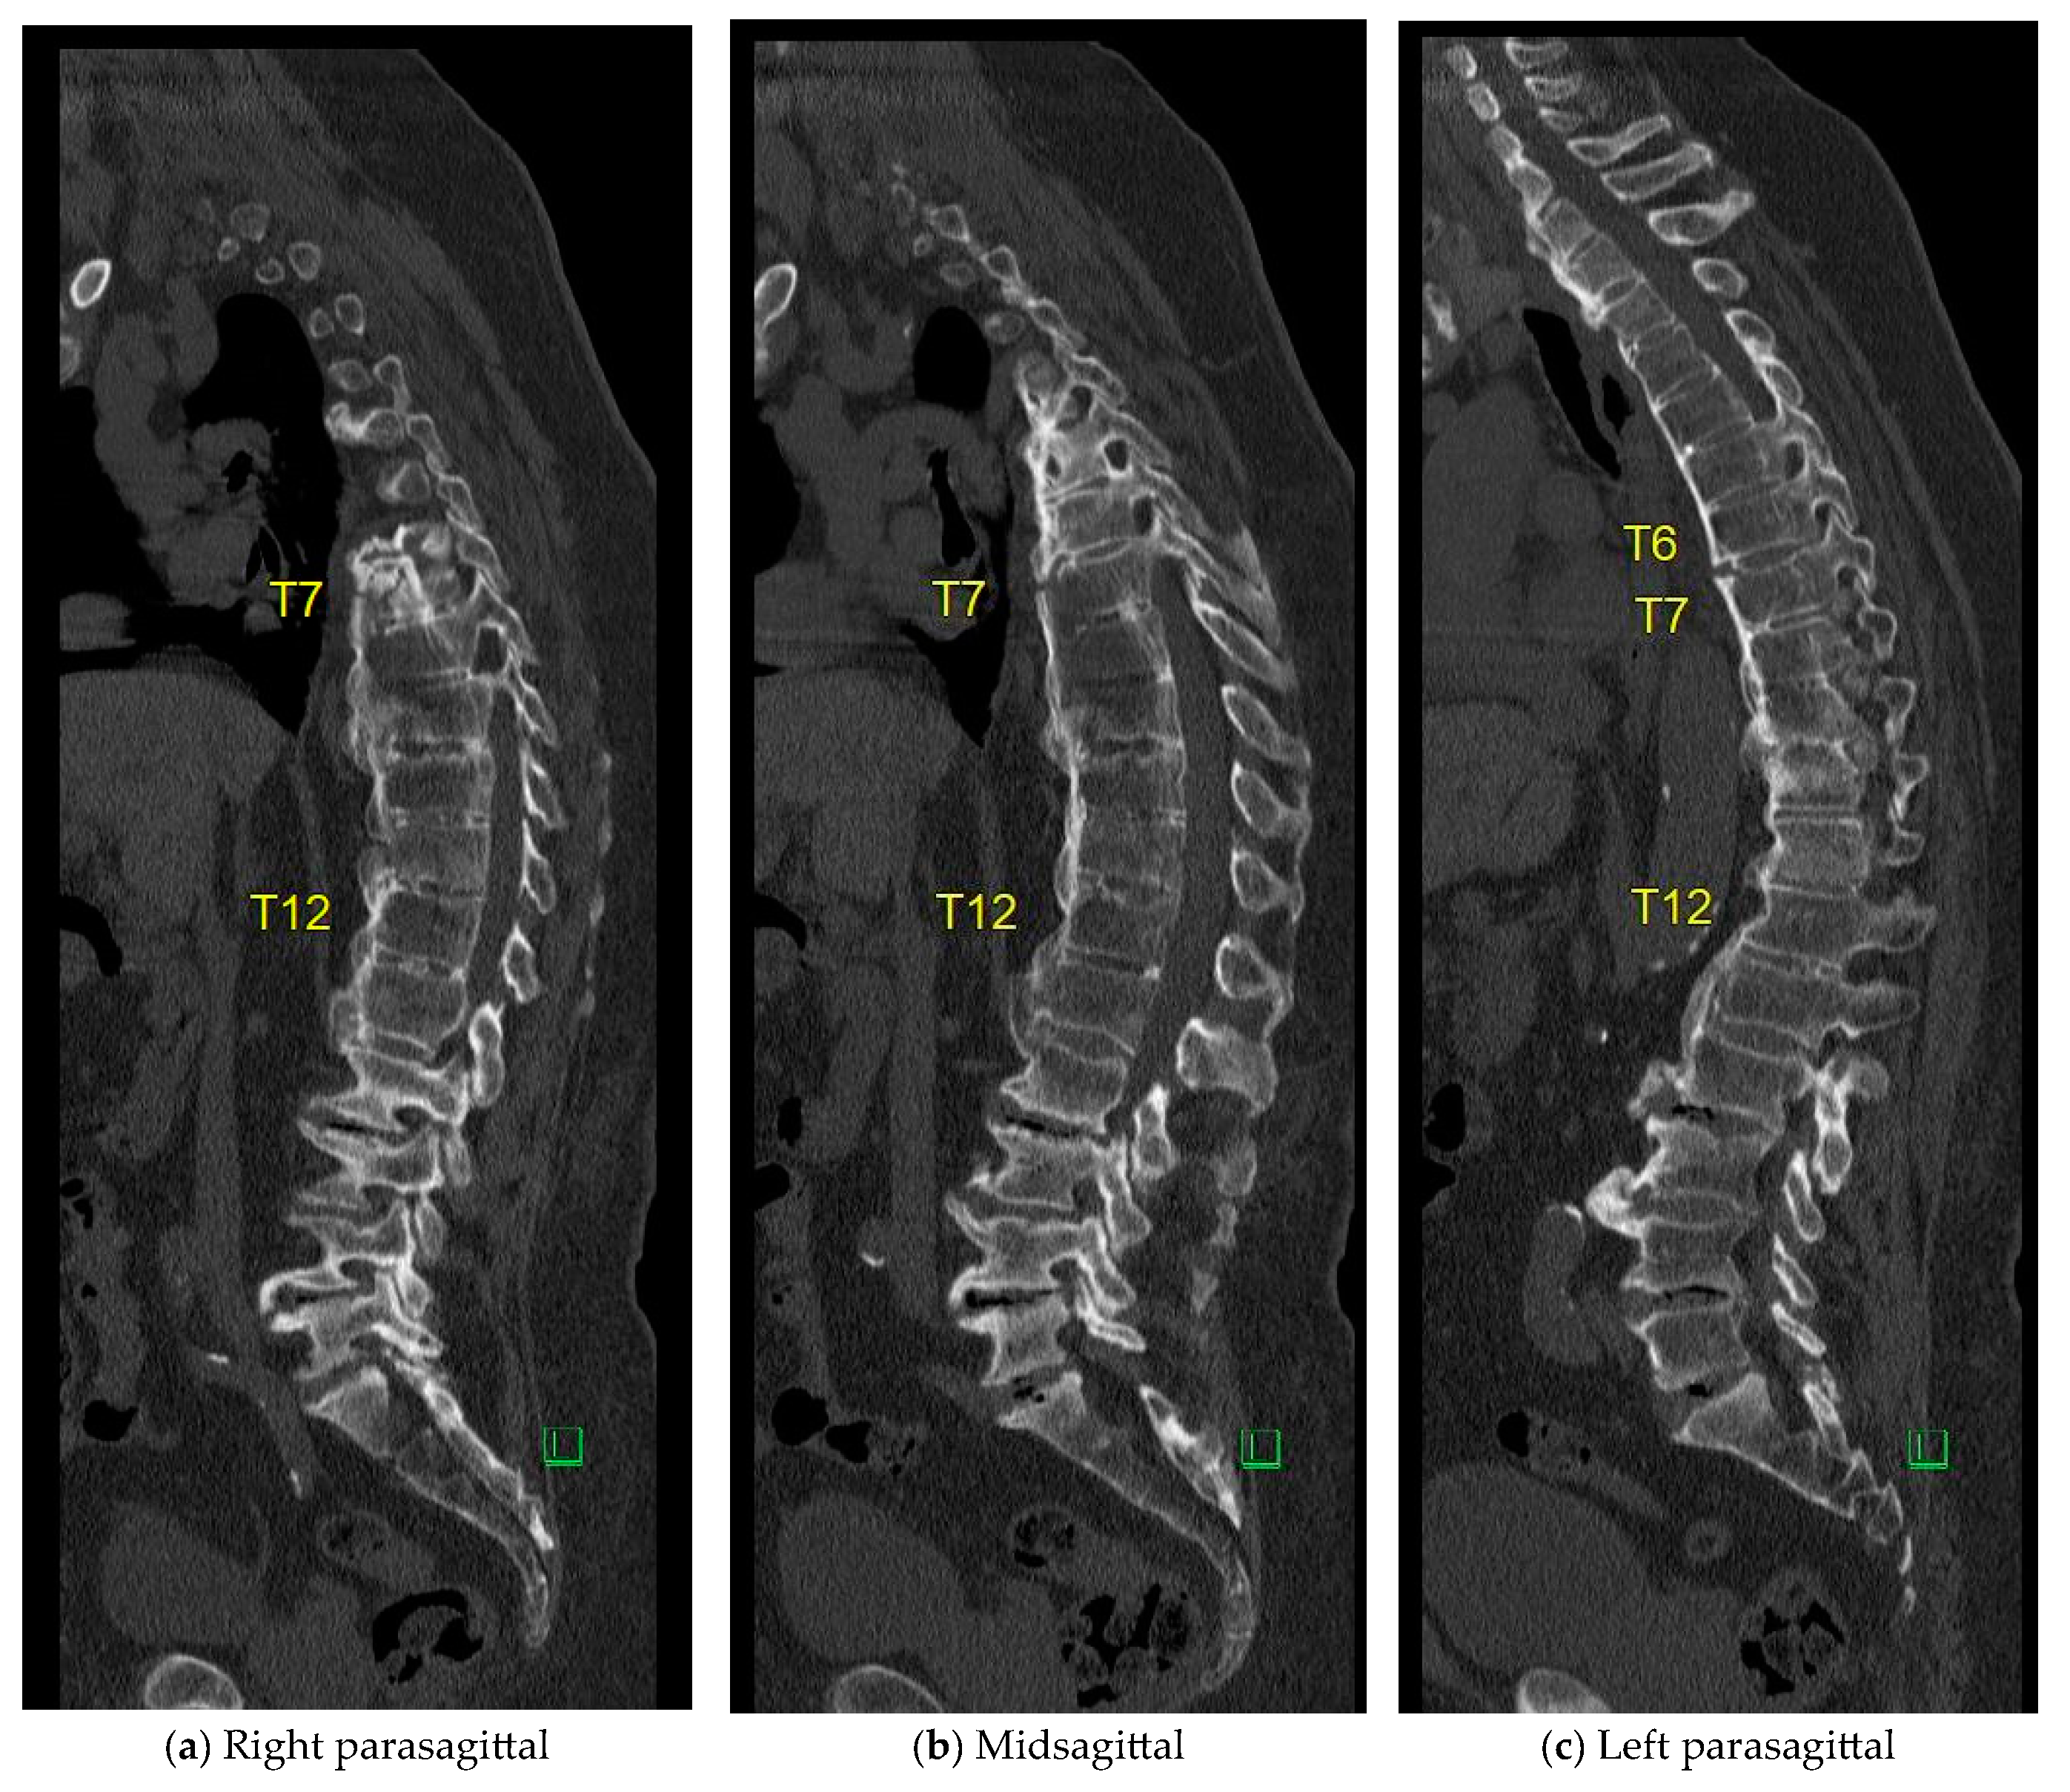

The case of an 81-year-old male, suffering from ischemic heart disease, atrial fibrillation, hypertension, morbid obesity, and gout, illustrates a unique treatment approach. He presented to the E.R. three days after a backward fall, having sustained an extension-type injury to T10–T11 a year and a half prior, which was treated non-operatively due to a very high operative risk. In the current fall, a new extension-type injury was identified at the T6–T7 level. He experienced back pain without radiating symptoms and had a long-standing foot drop but no new nerve deficit. His CT scans are shown in Figure A1. At a 4-month follow-up visit to the outpatient clinic, standing X-rays were performed, further confirming the stable healing of the fracture as shown in Figure A2.

Figure A1. Parasagittal (a,c) and Mid-sagittal (b) CT reconstructions obtained one year following a T9–T10 extension-type injury and five days after a subsequent backward fall. A new extension-type injury at the T6–T7 level is identified. No involvement of the posterior elements is observed.